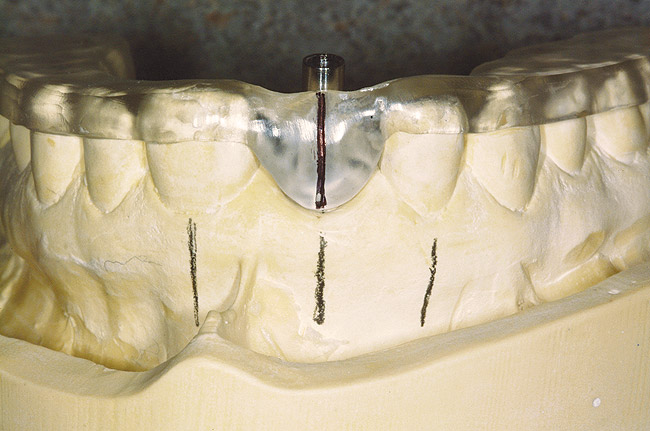

Figure 4  An example of a two-implant tissue bar for an implant-assisted prosthesis.

Figure 4

When dental implants were introduced by Brånemark, they were intended primarily for the completely edentulous patient, specifically the edentulous mandible. The initial prosthesis was a fixed restoration commonly referred to as a fixed bone anchored bridge. That particular prosthetic design is now the fixed-detachable hybrid prosthesis and has been highly successful for both the implants and prostheses.12,13 Implants have also been used for overdenture restorations14 and can be implant-assisted or implant-supported. With implant-assisted prostheses, the implants and mucoperiosteum share the forces of occlusion. A simple two-implant overdenture, either a Hader Bar® (Sterngold™, Attleboro, MA) or Locator® abutment (Zest Anchors, Escondido, CA), are examples of implant-assisted overlay prostheses and are always a removable restoration (Figure 4 and Figure 5). With implant-supported prostheses, the forces of occlusion are borne solely by the implants. This prosthesis can be an overlay prosthesis or a fixed restoration. Milled bar restorations, overdentures with bar substructures, and metal ceramic restorations attached to implant abutments by either screws or cement are examples of implant-supported restorations. One of the primary benefits of using dental implants in edentulous patients is the preservation of the residual bone, which will provide a better opportunity for future successful prosthetic restorations.